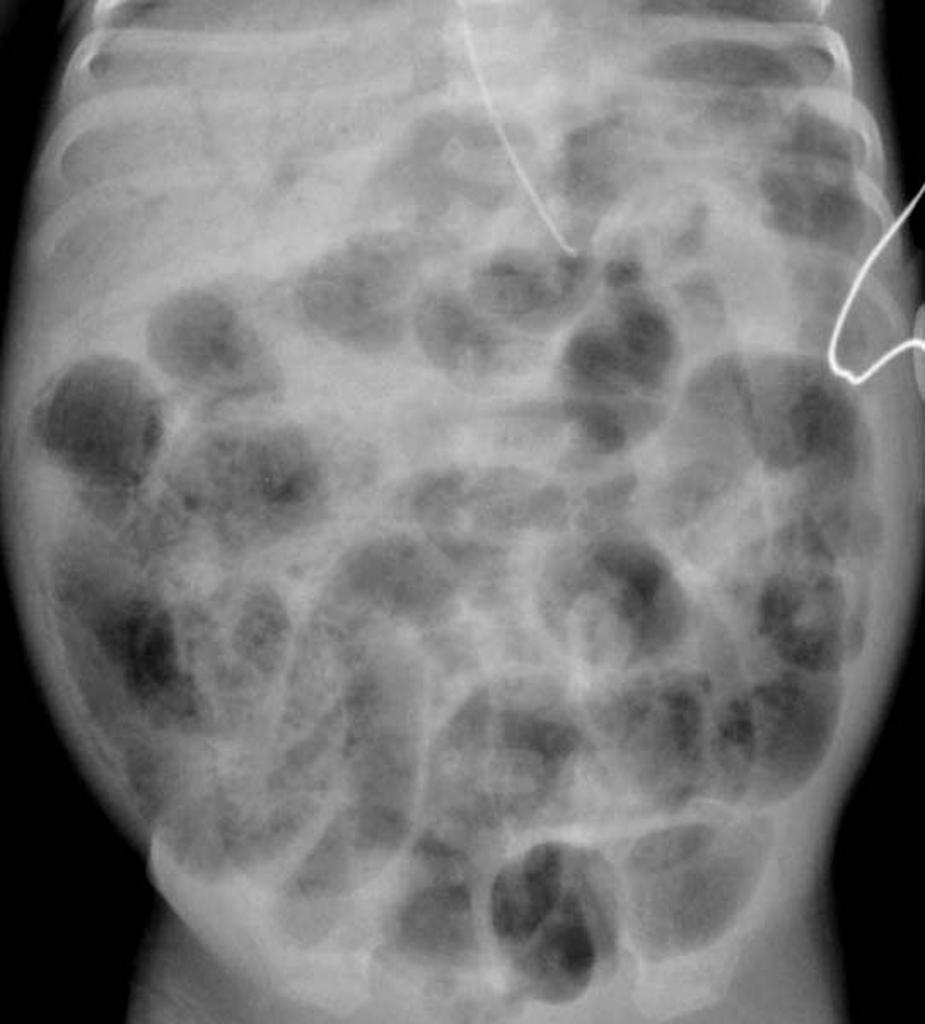

49. 一個十天大的早產兒,出生後有胎便解出,但在第四天大時陸續開始出現餘奶,這兩天發現有腹脹嘔吐的現象,且嘔吐物為綠色膽汁性。目前體重較出生體重少了15%。腹部x光如圖。以下敘述,何者不正確?

b. 診斷: abdominal radiographs that reveal intestinal distension with minimal air–fluid levels. Air remains trapped in the meconium------>no definite air–fluid interface.

Fine gas bubbles may be seen mixed within meconium, producing a characteristic soap-bubble appearance.